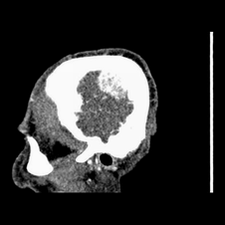

标题: CT25808:男,48岁,头痛多年,近段时间头痛加重伴步态不稳 [打印本页]

标题: CT25808:男,48岁,头痛多年,近段时间头痛加重伴步态不稳

平扫:右颞顶叶病灶呈等低密度伴大面积水肿,脑室受压变形。增强:病灶显著强化。考虑淋巴瘤或黑色素瘤。

1)不排除黑色素瘤可能;建议行mri检查。2)大脑镰下疝。3)脑积水(梗阻性)。